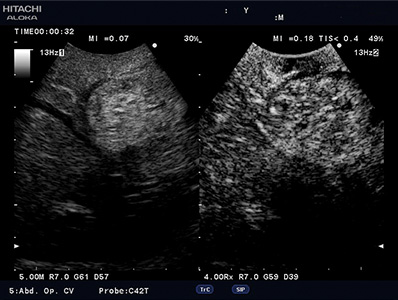

Contrast Harmonic Imaging (CHI)

Contrast-specific software is supported for use with contrast agents used with acoustic pressures from low to mid Ml. This is compatible with various transducers.